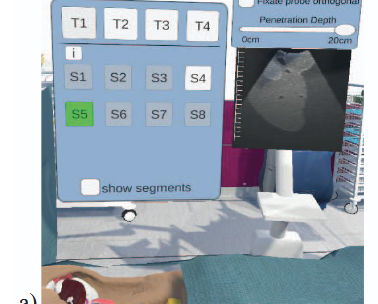

Virtual Reality for Surgery Planning

We are looking for a student interested in developing virtual reality (VR) applications using Unity for support of liver surgery planning. The VR project should include gamification aspects (like high scores etc.) to engage the medical users and increase their motivation.

The topic is suitable for a bachelor or master thesis.

Please contact: saalfeldlab [at] gmail.com